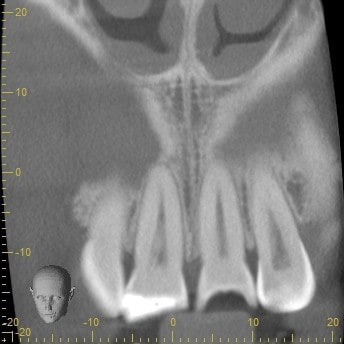

Lastly, I decided to take a CBCT to rule out any abnormality. To my surprise, a portion of the tooth had fractured off and become dislodged lingual to the tooth. Fortunately, the segment was removed easily and the patient’s symptoms resolved immediately.

The ability to take a CBCT and have it as part of our arsenal for diagnostic procedures is sometimes not readily appreciated. In this case, it was only through the CBCT that we could diagnose the cause of his symptoms and thereby treat the patient quickly.